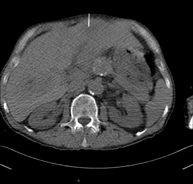

- Abdomen y pelvis- TC Abdomen Prueba diagnóstica que consiste en obtener imágenes del abdomen de alta definición anatómica (hígado, vesícula biliar, vía biliar, páncreas, bazo, estómago, intestinos, riñones, estructuras vasculares, vejiga, útero y ovarios, etc.) mediante el empleo de un equipo de TC (Tomografía Computarizada). Dichas imágenes se estudian posteriormente en una estación de trabajo que permite reconstrucciones bidimensionales en diferentes planos del espacio, y también reconstrucciones 3D (volumétricas). La mayoría de estudios requieren el empleo de contraste yodado para mejorar la definición de las imágenes. Prueba diagnóstica que consiste en obtener imágenes del abdomen de alta definición anatómica (hígado, vesícula biliar, vía biliar, páncreas, bazo, estómago, intestinos, riñones, estructuras vasculares, vejiga, útero y ovarios, etc.) mediante el empleo de un equipo de TC (Tomografía Computarizada). Dichas imágenes se estudian posteriormente en una estación de trabajo que permite reconstrucciones bidimensionales en diferentes planos del espacio, y también reconstrucciones 3D (volumétricas). La mayoría de estudios requieren el empleo de contraste yodado para mejorar la definición de las imágenes.

- TC Abdominopélvico Prueba diagnóstica que consiste en obtener imágenes bi y tridimensionales del abdomen y de la pelvis de alta definición anatómica (estructuras óseas, estructuras vasculares, hígado, páncreas, vesícula biliar, riñones, glándulas suprarrenales, bazo, intestino delgado y grueso, vejiga, útero y ovarios, próstata y vesículas seminales, uréteres, etc.) mediante el empleo de un equipo de TC (Tomografía Computarizada). La mayoría de estudios requieren el empleo de contraste yodado. Prueba diagnóstica que consiste en obtener imágenes bi y tridimensionales del abdomen y de la pelvis de alta definición anatómica (estructuras óseas, estructuras vasculares, hígado, páncreas, vesícula biliar, riñones, glándulas suprarrenales, bazo, intestino delgado y grueso, vejiga, útero y ovarios, próstata y vesículas seminales, uréteres, etc.) mediante el empleo de un equipo de TC (Tomografía Computarizada). La mayoría de estudios requieren el empleo de contraste yodado.